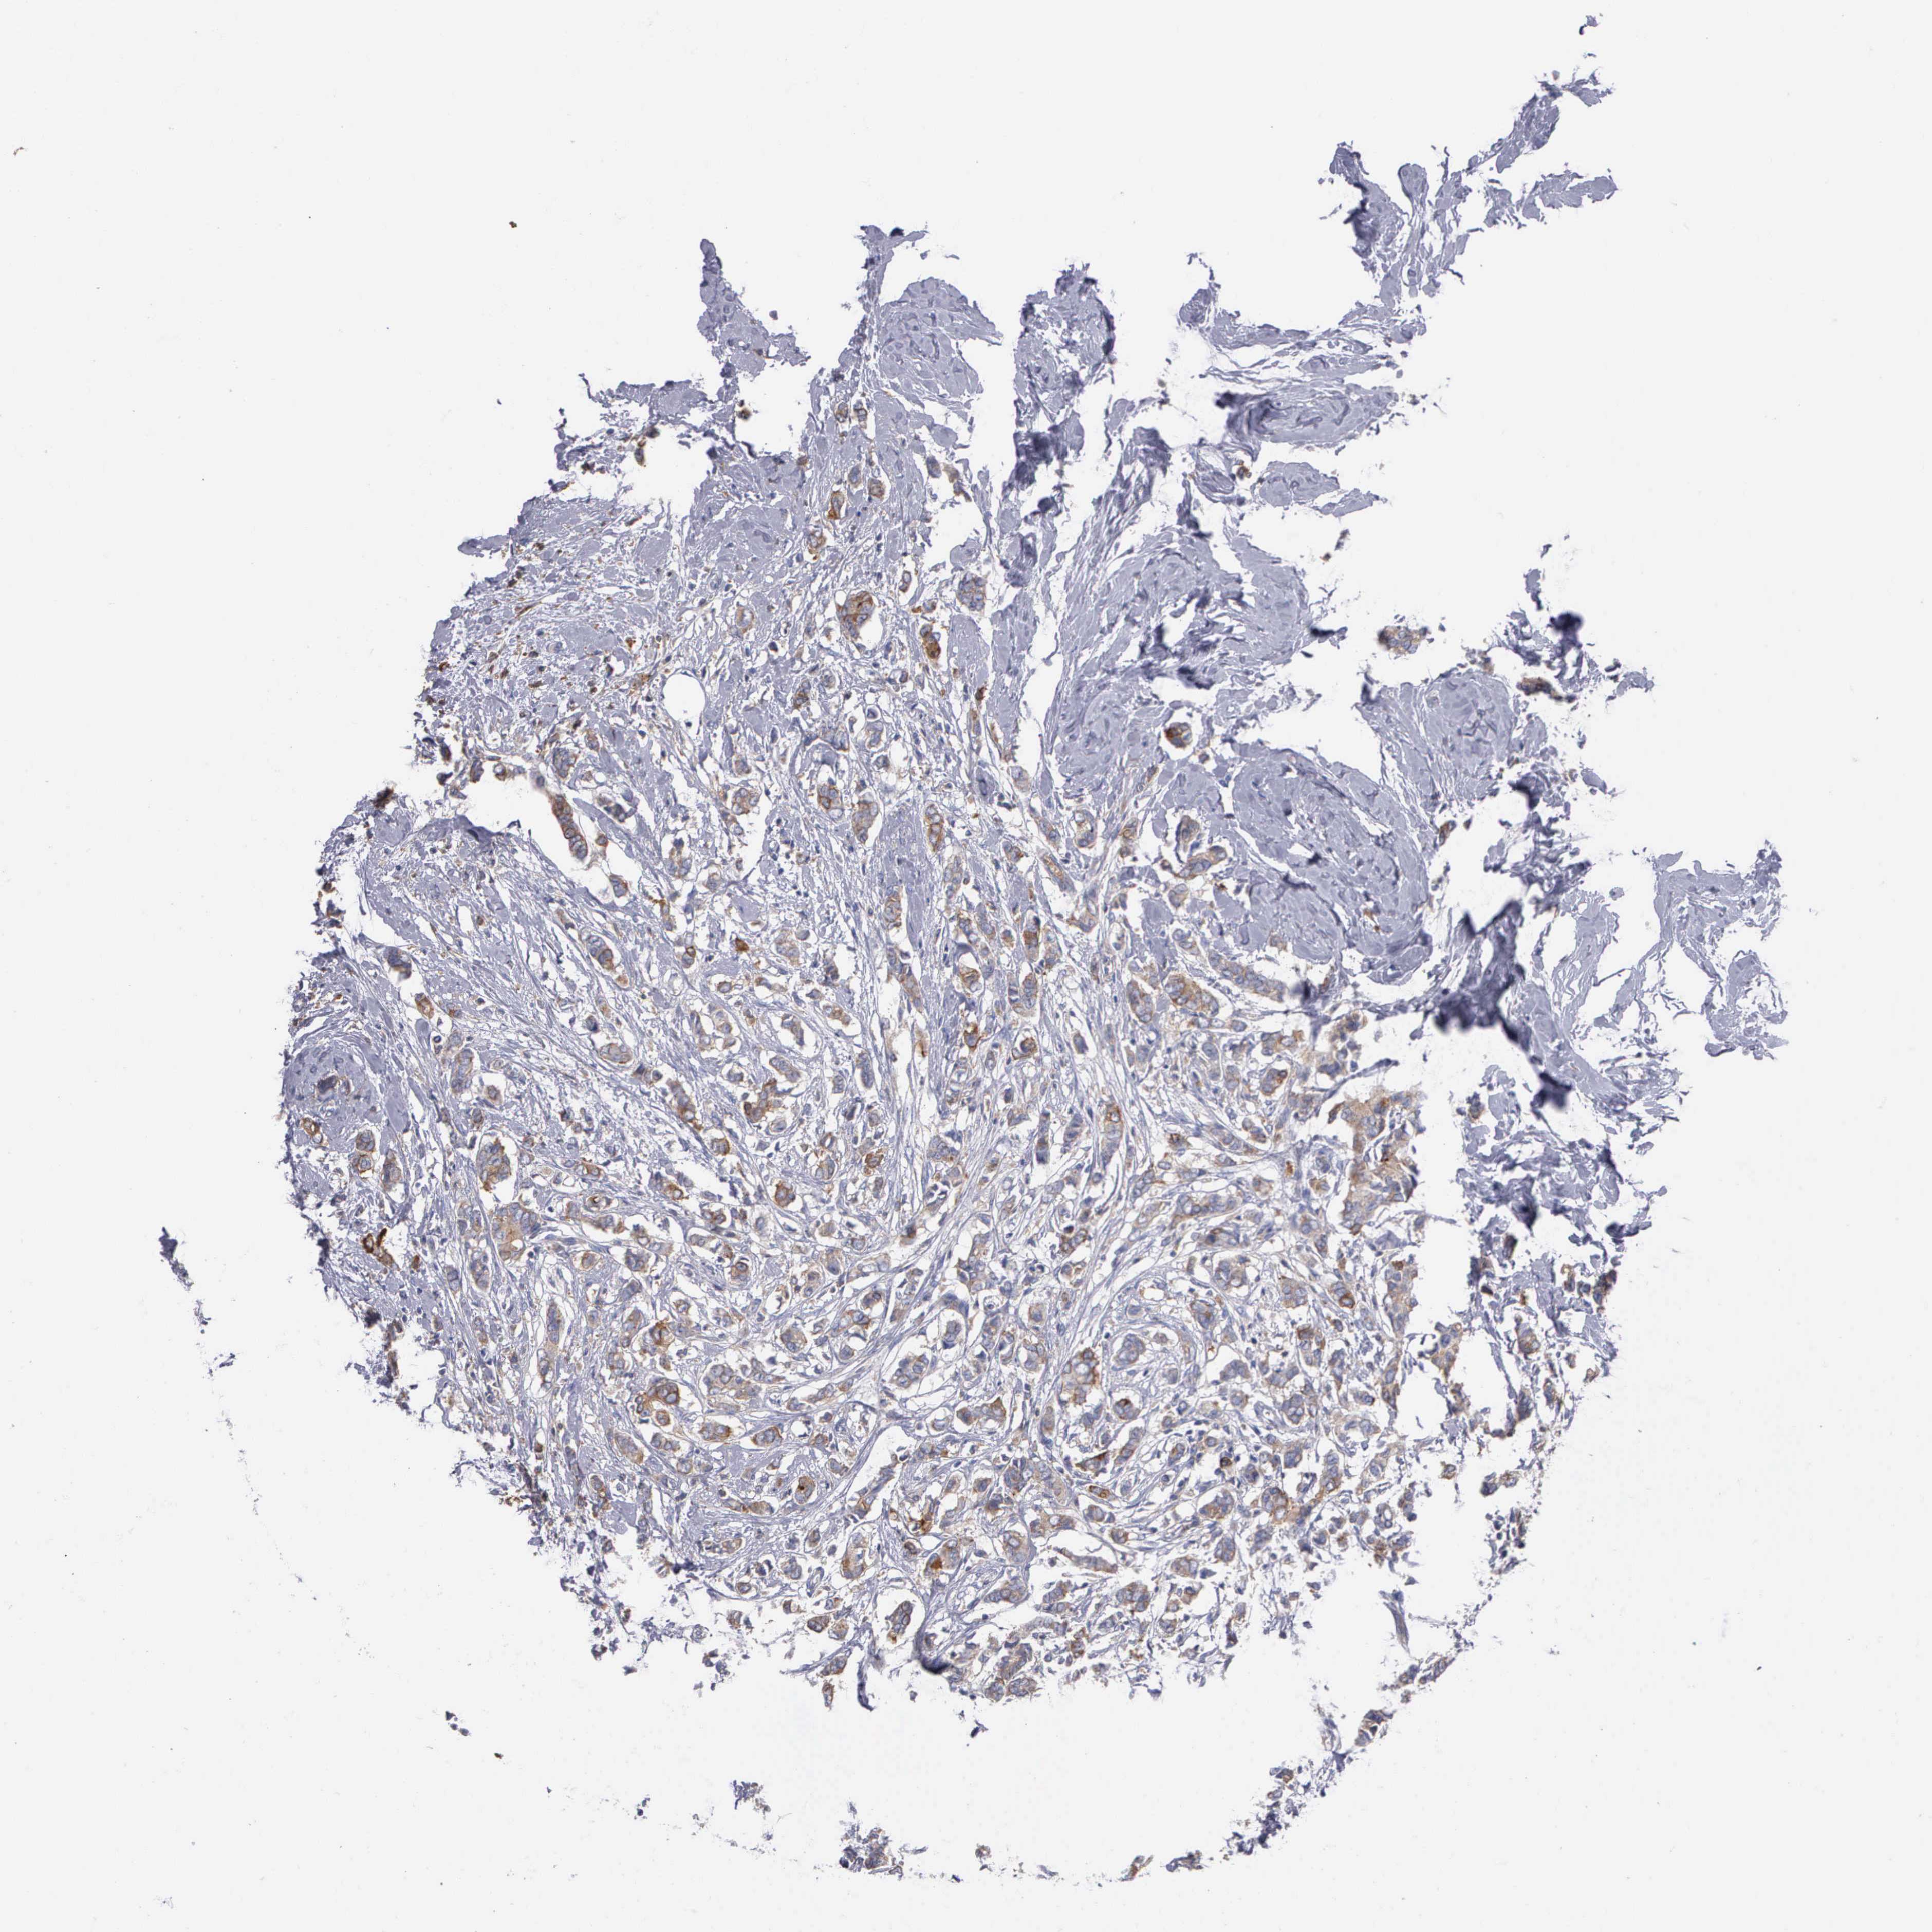

CANCER BREAST CANCER Show tissue menu

BRCA TCGA BRCA VALIDATION PROTEIN EXPRESSION

Breast cancer

Human cancer

Breast invasive carcinoma

PTGS2 is not prognostic in Breast Invasive Carcinoma (TCGA)

Average pTPM 2.3

Number of samples 1022